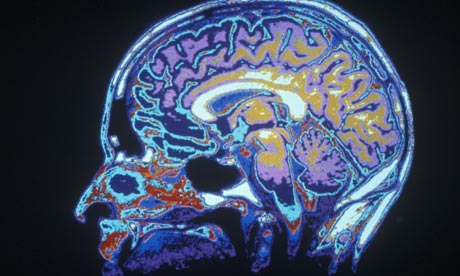

In the brain, epilepsy is an electrical storm. Waves of synchronized electrical activity spread through the cortex, usually emanating from one or more specific regions where the local neural wiring may have gone awry. While epilepsy can often be treated by medicines, in some instances surgery to remove the offending chunk of brain tissue is the only option. In these cases it is now becoming common to insert electrodes directly into the brains of surgical candidates, to better localize the ‘epileptic focus’ and to check that its removal would not cause severe impairments, like the loss of language or movement. And herein lie some remarkable new opportunities.

Recently, Dr. Picard used just this method to record brain activity from a 23-year-old woman who has experienced ecstatic seizures since the age of 12. Picard found that her seizures involved electrical brain-storms centred on a particular region called the ‘anterior insula cortex’. The key new finding was that electrical stimulation of this region, using the same electrodes, directly elicited ecstatic feelings – the first time this has been seen. These new data provide important support for previous brain-imaging studies which have shown increased blood flow to the anterior insula in other patients during similar episodes.